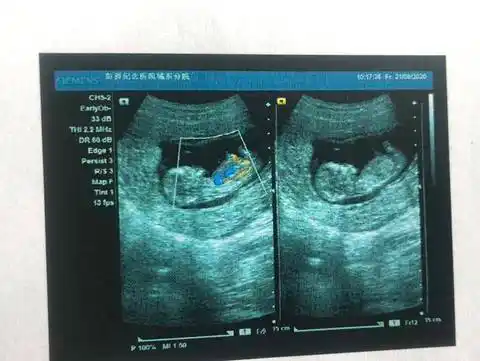

1cm,体重约16.4g,如图所示7070两胎儿的发育情况

12周加喜得双胞胎女儿真的又怕又惊喜